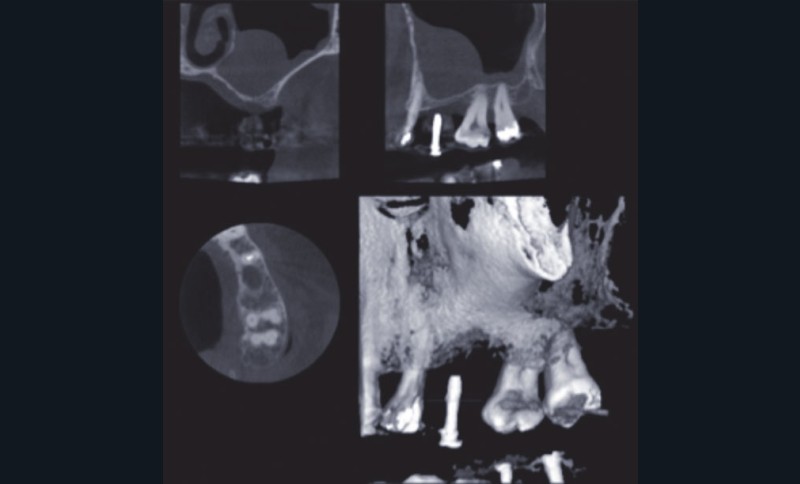

La largeur de la crête sera alors estimée mais seule l’analyse d’un cliché radiographique en 3D de type Cone Beam (CBCT) sera à même de préciser le volume osseux disponible. En cas d’insuffisance, de volume osseux vertical une élévation de sinus pourra être proposée (fig. 2).